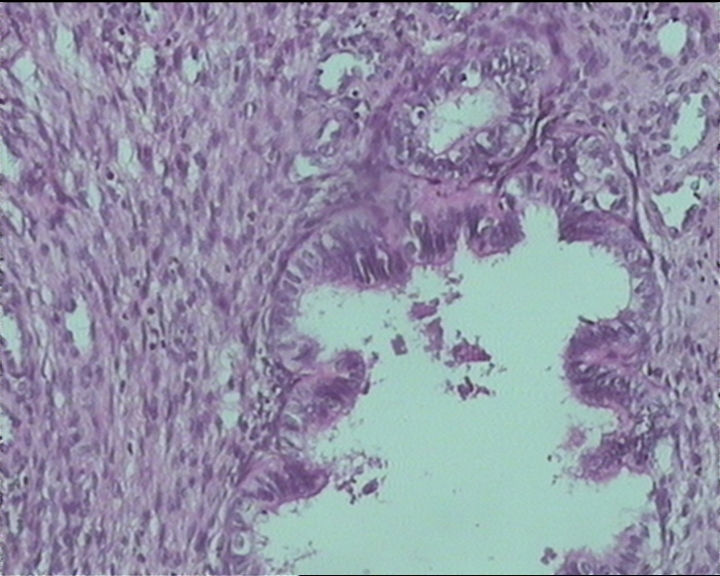

54岁女性,临床“宫颈息肉”送检;巨检:组织一块1。5*1CM,灰红。

细胞及腺体均有异形,图6、11、16象有纤维间质反应,考虑高级别上皮内瘤变/原位癌,腺癌不能除外。

输卵管粘膜化生

It is benign. Benign endocervical polyp with tubal metaplasia.

杨老师说它是良性的,是个颈管内膜息肉伴输卵管上皮化生,良性

Thanks for providing more photos from this case. If you are really concerning this case for dysplasia which is in the differential diagnosis, please perform a p16 immunohistochemistry to have a peaceful mind.

Sternberg病理学上诊断宫颈原位腺癌的标准是腺体的上皮去粘液分化,呈乳头状或筛网状增生,核分裂易见,这例显然达不到此标准。此例还是归入到腺上皮不典型增生为好。